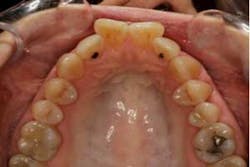

SFOT was used with a high-tech clear aligner to address hard- and soft-tissue deficiencies and severe maxillary and mandibular arch constriction.

A healthy, 57-year-old female presented with a lifelong desire for healthy, straight teeth and a beautiful smile. She had been told numerous times that it was not possible without premolar extractions.

SFOT surgery was performed in the maxillary and mandibular arches with deep buccal corticotomies. Particulate, demineralized, freeze-dried bone allograft and acellular dermal matrix were used to augment the ridges.

Total treatment time: 6 months. Patient declined recommended further clear aligner refinement and fine-tuning periodontal plastic surgery.